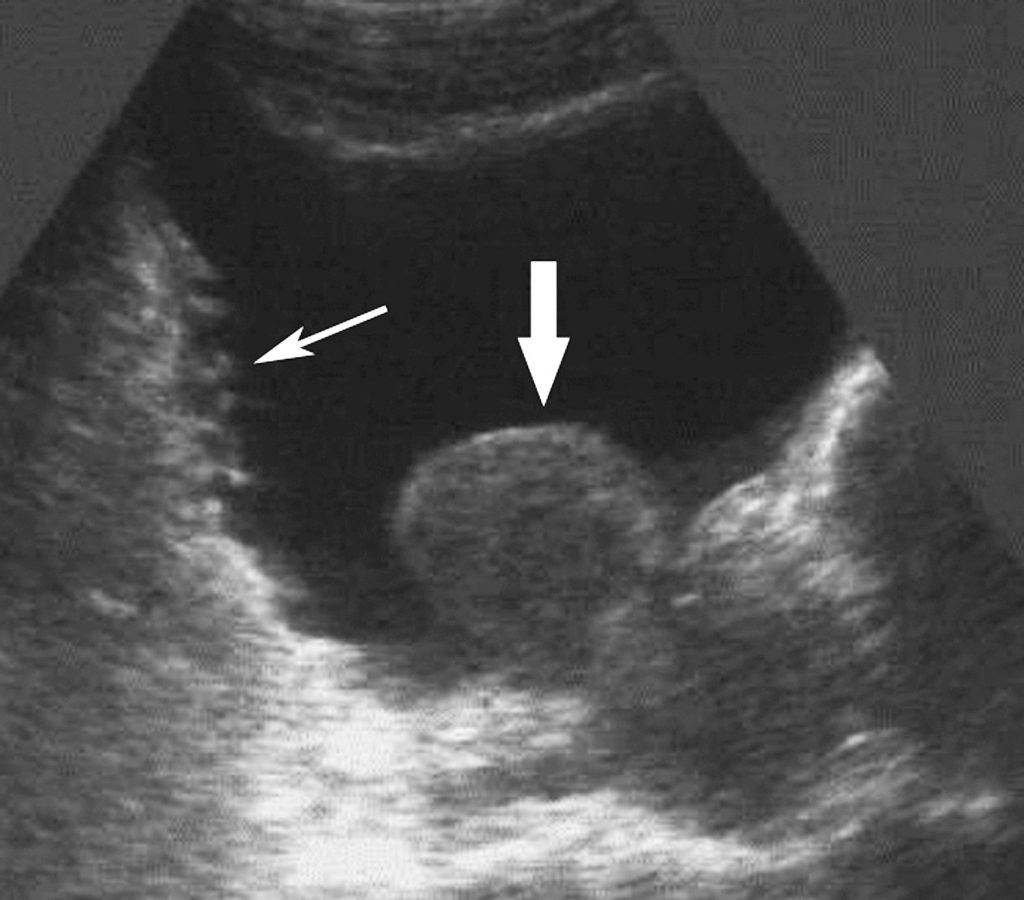

- le retentissement vésical (figure 25.2) :

Fig. 25.2. Échographie pelvienne par voie sus-pubienne ; plan sagittal.

Examen réalisé en post-mictionnel. Hypertrophie prostatique avec lobe médian (masse échogène avec extension intravésicale ; flèche large) et vessie de lutte (paroi vésicale irrégulière « à cellules et colonnes » ; flèche fine). La vessie est encore pleine (RPM estimé à 250 cm3).

Source : CERF, CNEBMN, 2022.

– mesure du volume du RPM ;

– recherche d’une vessie de lutte, associant :

-hypertrophie pariétale vésicale ;

– parois irrégulières, trabéculées ;

– diverticules vésicaux) ;

- la recherche de calculs vésicaux.